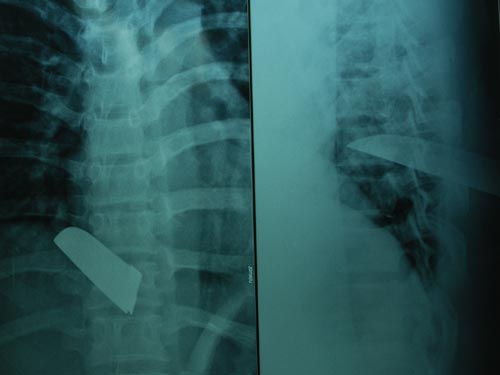

(NLĐO)- Ngày 28-2, các bác sĩ Bệnh viện Nhân dân 115 cho biết bệnh viện vừa cứu sống một nam thanh niên bị đâm thủng tim, phổi.

Bệnh nhân bị tổn thương tim, phổi có nguy cơ tử vong rất cao

Theo bác sĩ Cao Văn Thịnh, Trưởng Khoa Lồng ngực - Mạch máu, bệnh nhân có nguy cơ tử vong rất cao do bị sốc mất máu, suy hô hấp và nhập viện muộn.

Trước đó, rạng sáng 18-2, bệnh nhân Đ.Q.T. (38 tuổi, ngụ TPHCM) được chuyển đến Bệnh viện Nhân dân 115 từ một phòng khám tại quận Bình Tân trong tình trạng khó thở, ngực trái có vết thương dài 4 cm xuyên thấu phổi trái và thủng tâm thất trái 1 cm gây tràn máu khoang màng tim, phổi.

Các bác sĩ xử trí cấp cứu vá những vết thủng, dẫn lưu màng phổi, cứu sống bệnh nhân. Hiện sức khỏe bệnh nhân tạm ổn. T. cho biết anh bị đâm bằng vật sắc nhọn tại một quán cà phê sau khi xảy ra xô sát, ẩu đả.

Cũng theo bác sĩ Thịnh, hiện số bệnh nhân bị vết thương tim đang tăng lên, đa số là nam giới. Nguyên nhân chủ yếu do vật sắc nhọn gây ra. Việc điều trị phẫu thuật những ca này thành công hay không phụ thuộc vào nhiều yếu tố như thời gian nhập viện, mức độ tổn thương, có kết hợp tổn thương nhiều cơ quan hay không...